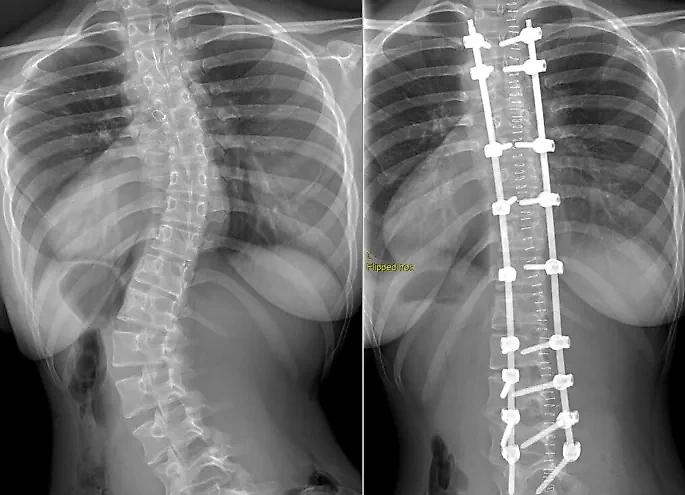

Спина Полины до и после операции. Фото © НИИТО имени Я.Л. Цивьяна

Полина Колупанова с рождения имела тяжёлый порок сердца, из-за которого организм недополучал кислород. Девочку прооперировали ещё в младенчестве, но с возрастом выявилась сопутствующая проблема — одно плечо постоянно было ниже другого. Сколиоз развивался и перешёл в четвёртую стадию.

В 2020 году новосибирские врачи провели школьнице четырёхчасовую операцию. Позвоночник был зафиксирован в правильном положении при помощи металлического каркаса. Девочка сразу почувствовала себя лучше и призналась, что теперь преодолеет любые жизненные трудности. Она поблагодарила своих хирургов Дениса Николаевича Долотина, Александра Юрьевича Сергунина, профессора Михаила Витальевича Михайловского, анестезиолога Анастасию Александровну Иванову и всех медсестёр.